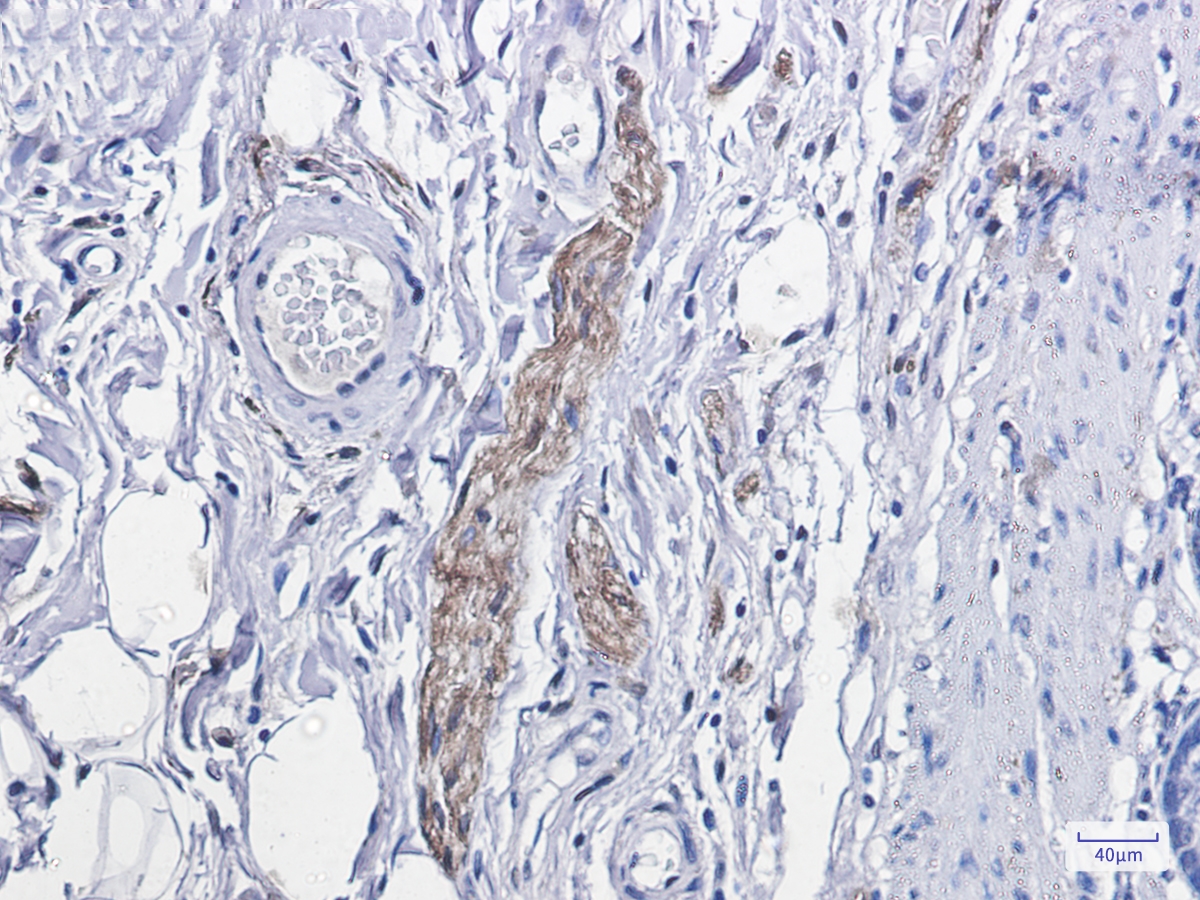

Immunohistochemistry of Phospho-PKC alpha (Thr638) in paraffin-embedded human colon cancer tissue using Phospho-PKC alpha (Thr638) Rabbit mAb at dilution 1/100